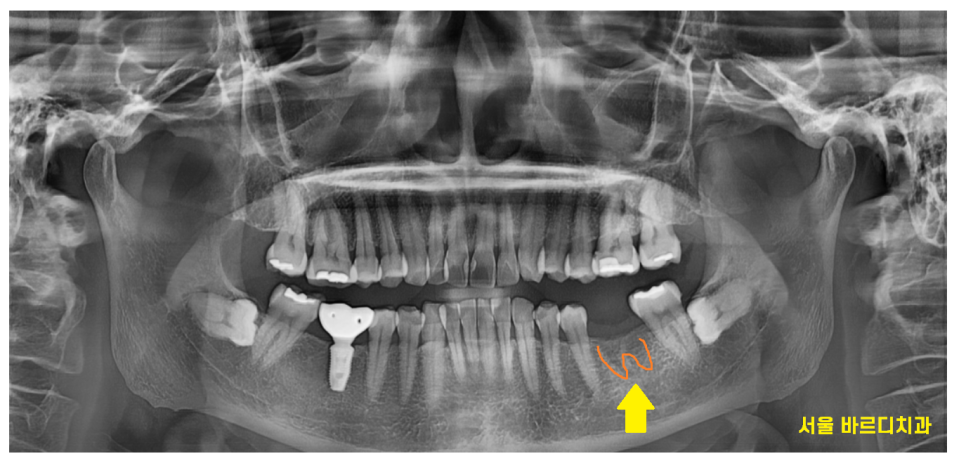

1차적으로만 파노라마 사진을 보았을 때

뼈 이식

제가 보기에는 필요 없어보였습니다.

24.01.11

제가 놓치는 부분이 있을까

ct까지 찍어보았지만

뼈 이식 해야할 이유가 전혀 없었습니다.